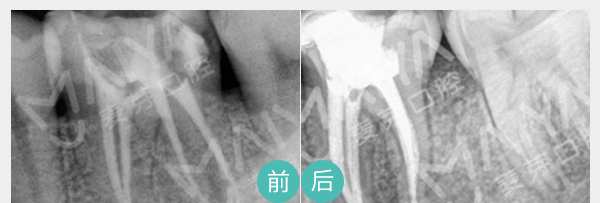

麦芽显微根管治疗

通过机械和化学方法去除根管内的大部分感染物,并通过充填根管、封闭冠部,防止发生根尖周病变或促进已经发生的根尖周病变的愈合。

适应症:牙根尖周炎